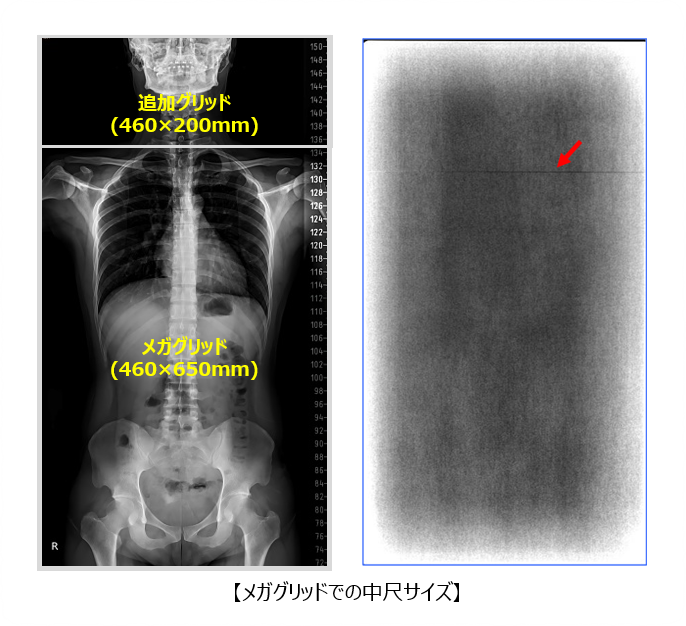

■メガグリッド

従来、長尺・中尺サイズのグリッドは、2~3枚を連結して製造されていました。

そのため、連結部が画像中心付近に位置し、主要な患部が映る中心部と干渉するという課題がありました。

当社では、グリッドの製造可能サイズを最大680×680mmまで拡大する技術を開発し、連結部を任意の位置に配置することで、画像中心部と干渉しないグリッドの製造を実現しています。